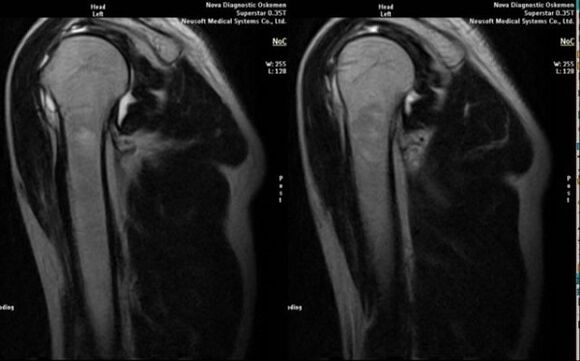

- μαγνητικός συντονισμός και αξονική τομογραφία.

Σημάδια που υποδεικνύουν άμεσα την ανάπτυξη αρθρώσεως είναι η εμφάνιση σημαντικής στένωσης του αρθρικού χώρου, σκλήρυνση των υποχόνδρινων δομών, λέπτυνση της ίδιας της στιβάδας των χονδροκυττάρων, εμφάνιση οστεοφύτων και εναπόθεση κρυστάλλων άλατος στο ενδοαρθρικό υγρό.